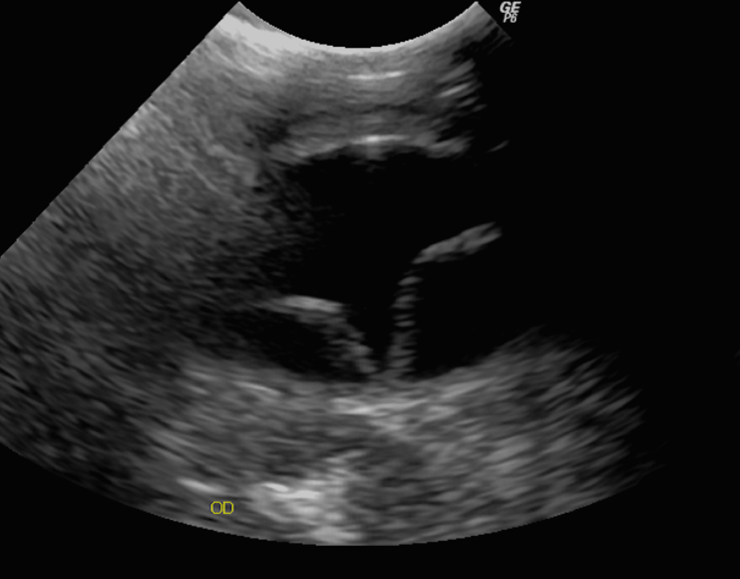

各種検査より腎性高血圧による網膜剥離と診断しました。

超音波検査にて網膜剥離を確認した